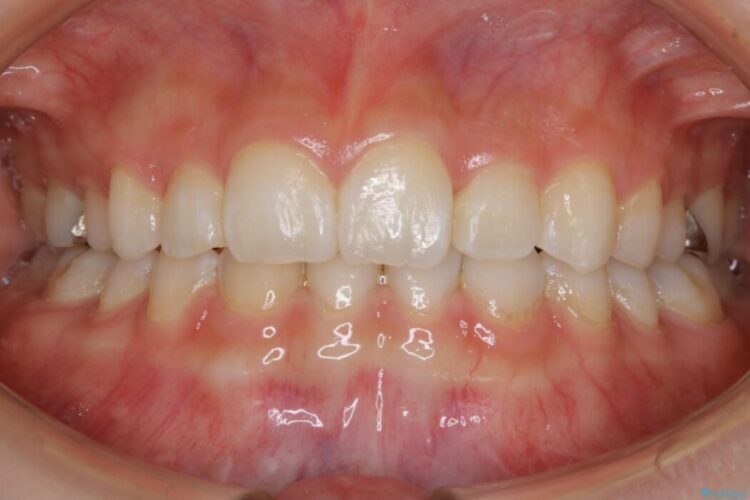

治療後について

笑った時の歯の見た目がきれいになりとても喜んでいただけました。